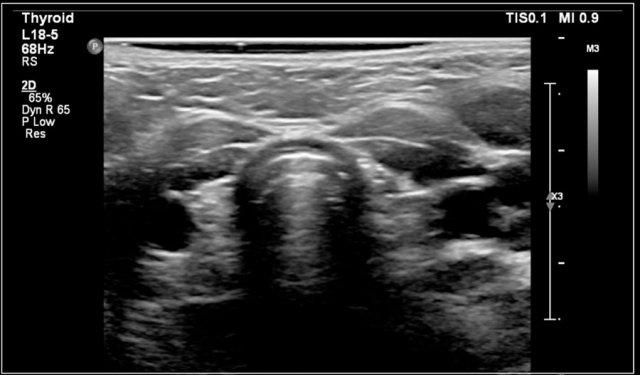

Đây là hình ảnh của một bé gái 16 tuổi mắc cường giáp.

Tuyến giáp to lan tỏa với tình trạng sung huyết.

Chẩn đoán cuối cùng là bệnh Graves.

Bệnh nhân được điều trị bằng I-131.